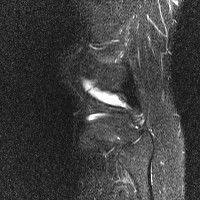

무릎 mri 간단히 봐주실 수 있으시나요 ㅠㅠ

안녕하세요 8년전 십자인대 수술하고 최근 무리한 운동에 무릎 불편감이 생겨서

mri 찍었습니다.

진단결과는 첫 찍은 병원에서 활액막염 이라는 진단을 받았습니다. 혹시 봐주실 수 있으실까요?

올라온 MRI가 단편적이라서 정확한 진단에 어려움이 있지만 십자인대에는 큰 이상이 있지는 않은것 같으며, 무릎관절내 물이 있는 것으로 보아 활액막염의 진단이 맞을 것 같습니다.

하지만 단편적인 영상이기 때문에 촬영병원에서 정확한 판독지 등을 받으시는 것이 좋겠습니다.